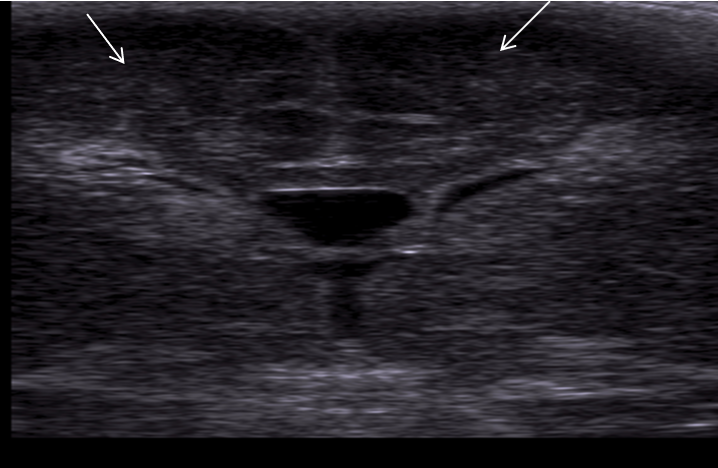

Neonatology Grade 1 PVL 3 Image